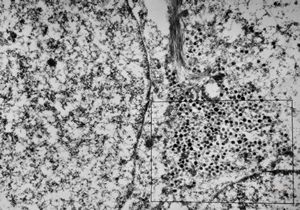

F, 24y. | molluscum contagiosum … virions

F, 24y. | molluscum contagiosum

F, 7y. | molluscum contagiosum … virions